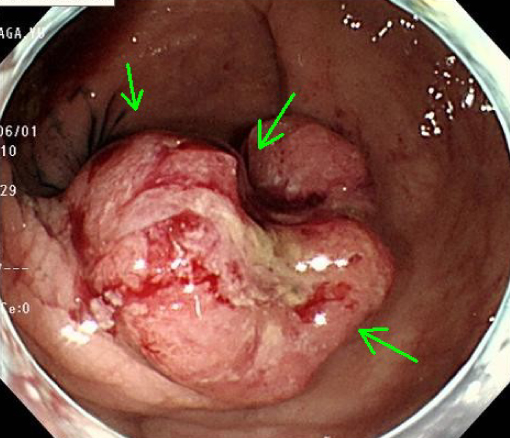

• 大腸がん

写真は進行がんです。

進行した大腸がんは手術(開腹手術)で治療します。